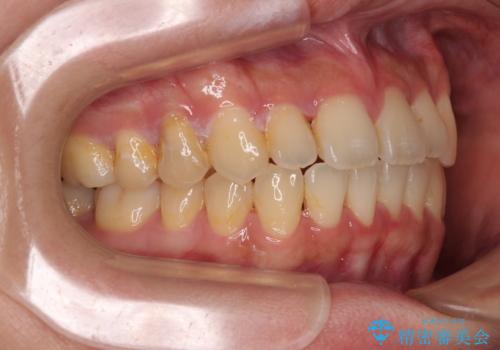

- 上下前歯のデコボコやクロスバイトを気にして来院された患者様です。

上顎歯列が下顎の歯列に対して狭小であり、一部下顎の奥歯が上顎よりも外側に位置している状態でした。

上顎の急速拡大装置を使用して上顎骨を側方に拡大することで上顎歯列を拡大し、下顎歯列も拡大できるようにすることで、歯列を整えることとしました。

歯列矯正では基本的に骨格を改善することはできませんが、急速拡大装置(MARPE)を使用することで上顎骨を側方に拡大させることができ、咬合状態を大きく改善することができます。